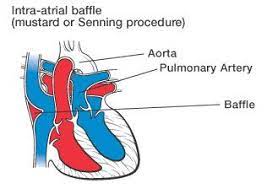

Overview

Package includes:

Days in hospital : 7 to 8 Days (For patient and one attendant)

Days in hotel : 14 Days (For patient and one attendant)

Room type in hospital : Shared

Room type in hotel : Private

Hotel category: Standard

Value added benefits of the Senning Repair:

Ø Doctor consultation charges

Ø Lab tests and diagnostic charges

Ø Room charges inside hospital during the procedure

Ø Surgeon Fee

Ø Nursing charges

Ø Hospital surgery suite charges

Ø Anesthesia charges

Ø Routine medicines and routine consumables (bandages, dressings etc.)

Ø Food and Beverages inside hospital stay for patient and one attendant.

Extra benefits:

ü Interpreter

ü Visa assistance

Ø Site tourism of the city

Ø Follow up with the doctor

Ø Airport pick up and drop

Ø Free online consultation with the doctor

Ø Priority appointments with the doctor

Ø Room upgrade from sharing to private

Overview

Package includes:

Days in hospital : 10 to 11 Days (For patient and one attendant)

Days in hotel : 14 Days (For patient and one attendant)

Room type in hospital : Shared

Room type in hotel : Private

Hotel category: Standard

Value added benefits of the Senning Operation:

Ø Doctor consultation charges

Ø Lab tests and diagnostic charges

Ø Room charges inside hospital during the procedure

Ø Surgeon Fee

Ø Nursing charges

Ø Hospital surgery suite charges

Ø Anesthesia charges

Ø Routine medicines and routine consumables (bandages, dressings etc.)

Ø Food and Beverages inside hospital stay for patient and one attendant.

Extra benefits:

ü Interpreter

ü Visa assistance

Ø Site tourism of the city

Ø Follow up with the doctor

Ø Airport pick up and drop

Ø Free online consultation with the doctor

Ø Priority appointments with the doctor

Ø Room upgrade from sharing to private